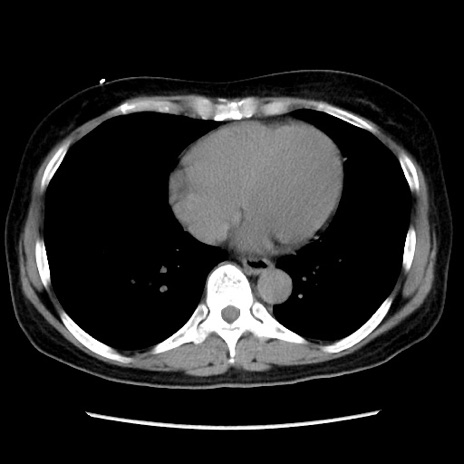

症例10(横断像)

【症例】 50歳代女性

【主訴】 腹痛

【現病歴】前日生レバーを食べた。今朝に排便あり。 昼前に突然発症の腹痛を生じ、当院救急外来を受診した。

【既往歴】 子宮筋腫にてで子宮全摘後

【身体所見】 意識清明、腹部:平坦、軟、下腹部やや左を中心に圧痛・反跳痛あり、筋性防御あり

【データ】WBC 7800、CRP 0.07